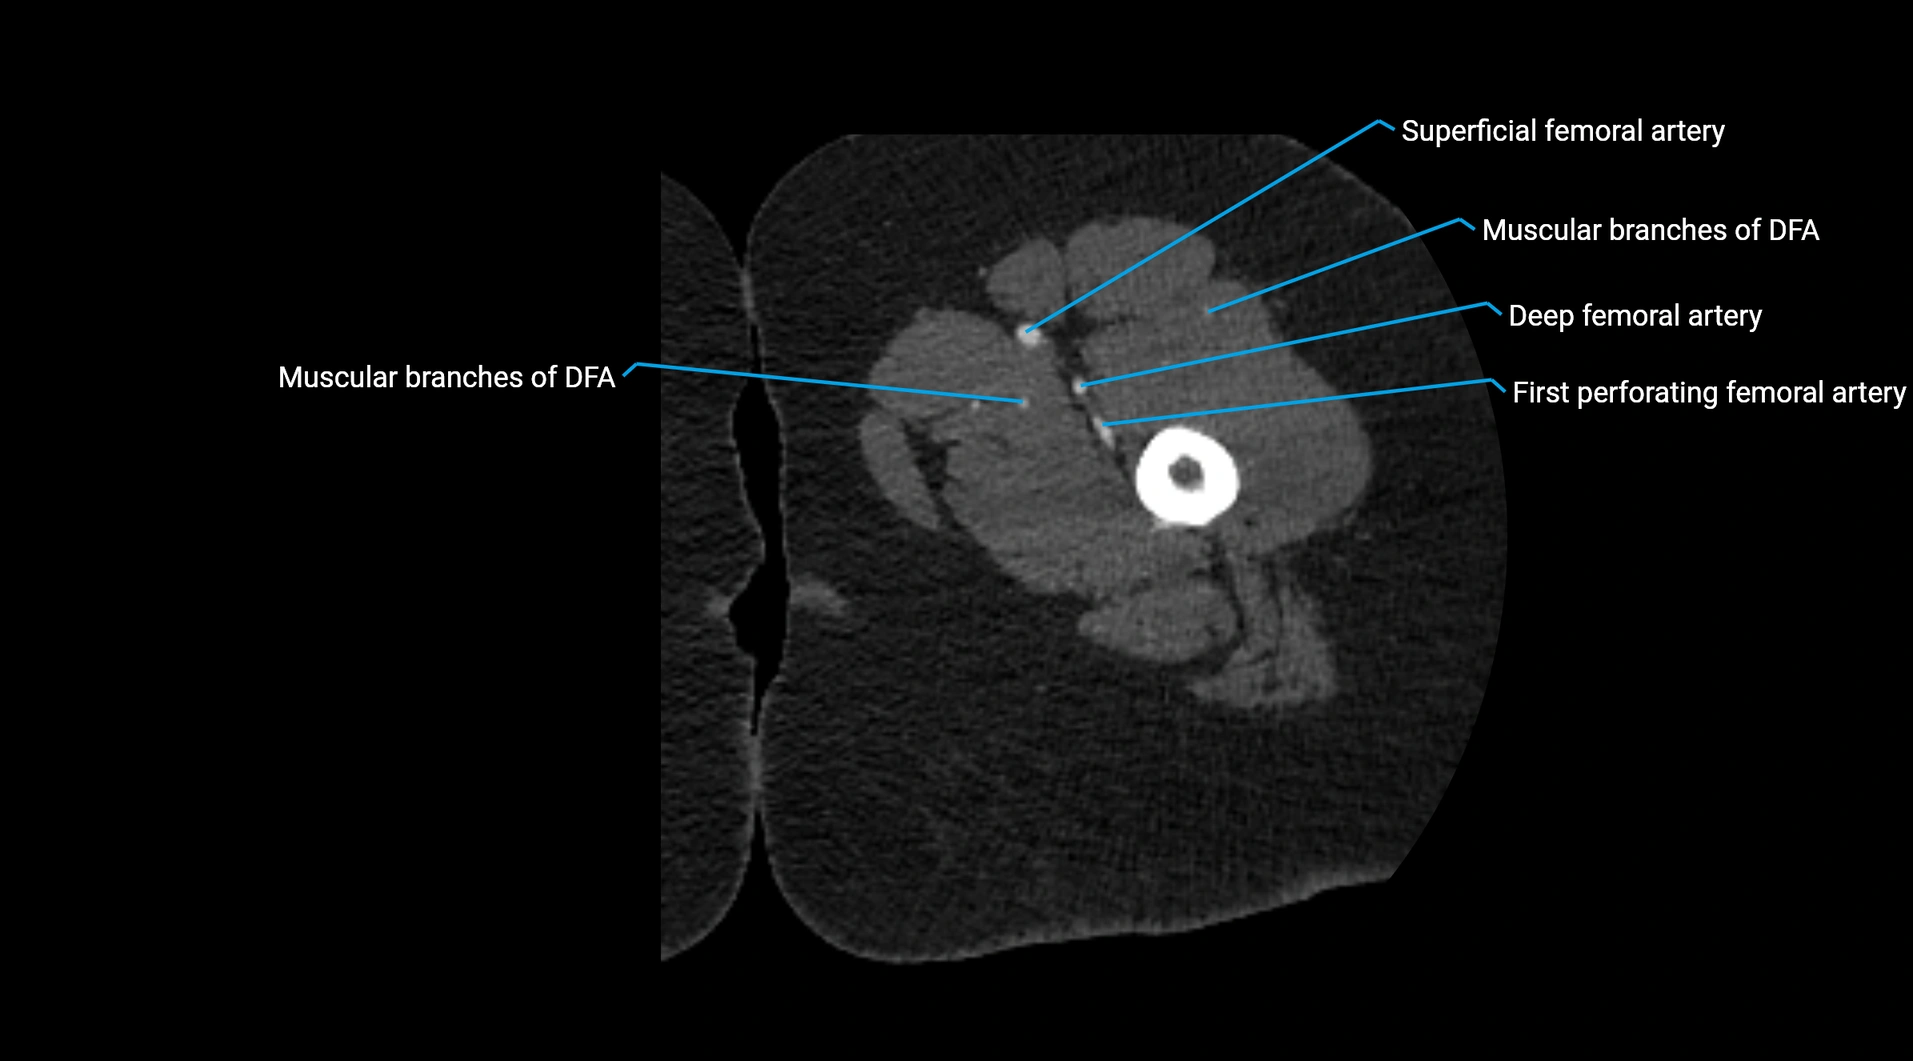

CT Appearance

Non-contrast CT:

• Appears as a tubular soft tissue structure anterior to vertebral bodies

• Calcified atherosclerotic plaques appear as hyperdense foci along the wall

• Useful for screening abdominal aortic aneurysm (AAA) size and mural calcification

Contrast-enhanced CT (CTA):

• Gold standard for abdominal aortic imaging

• Provides excellent detail of lumen, wall, aneurysm, thrombus, and branch vessels

• Multiplanar and 3D reconstructions help in aneurysm measurement, stent graft planning, and dissection evaluation

• Detects acute rupture, traumatic injury, or occlusion with high sensitivity